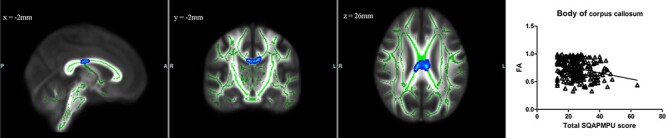

TBSS analysis revealed that the FA in the body of the corpus callosum was negatively correlated with SQAPMPU score, and we did not find that MD, AD or RD was correlated with SQAPMPU score (Figure 2).

Fig. 2.

The blue-light blue colour indicates negative correlation between SQAPMPU score and FA in the body of corpus callosum (P < 0.05, TFCE corrected). Green represents mean FA skeleton of all participants. x, y, z is MNI coordinate. The scatterplots show the association between SQAPMPU score and FA values that are extracted from significant clusters of each subject.

In addition, TBSS analysis found that FA of the body of the corpus callosum was negatively correlated with SQAPMPU score. Reduced WM integrity of the corpus callosum has been associated with many addictive behaviours (Pfefferbaum et al., 2010; Jeong et al., 2016). Our result was consistent with previous studies of Internet addiction, which found reduced FA in the corpus callosum in Internet-addicted adolescents compared to controls (Bi et al., 2015). Moreover, He et al. (2018) found the excessive social media use was correlated with abnormal WM integrity of the corpus callosum. Thus, it is possible that PMPU is related to inter-hemispheric communication deficits.